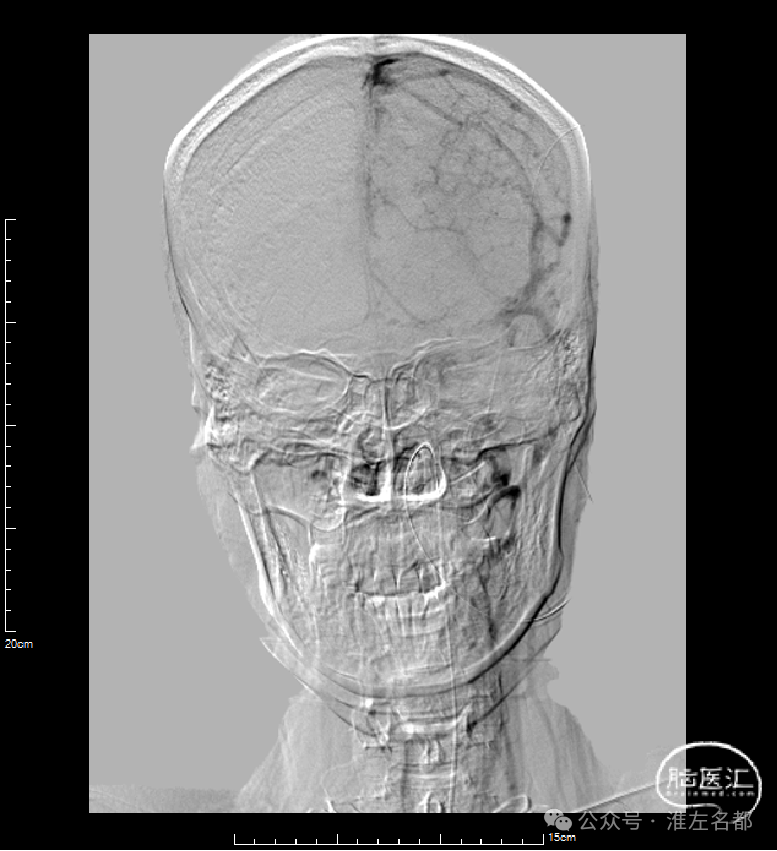

右侧颈动脉造影(正侧位):上矢状窦和直窦未见显影;右侧横窦和乙状窦少许显影。

左侧颈动脉造影(正侧位):上矢状窦前部少许显影,直窦未见显影,左侧横窦和乙状窦显影纤细。